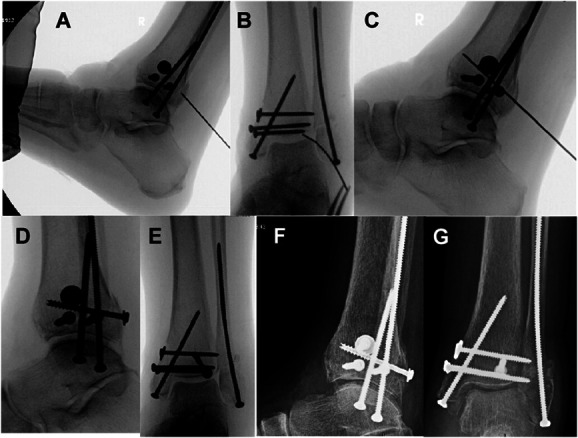

后踝骨骨折(PMFs)(OTA 43B1.1)经常与腓骨、内侧踝骨和胫骨远端骨折同时发生,很少单独出现。PMF 会影响踝关节臼的对齐和巩膜的稳定性。用于固定PMF的技术包括通过后外侧或后内侧方法进行开放复位内固定,或进行前后螺钉固定。对于选定的微移位或无移位的后踝骨骨折,我们开发了一种经皮技术,通过跟腱插入后至前插管螺钉。本文对该技术进行了描述,并回顾了一系列临床案例。

Posterior malleolus fractures (PMFs) (OTA 43B1.1) are frequently seen in combination with fractures of the fibula, medial malleolus, and distal tibia; they can rarely be seen in isolation. PMFs affect the alignment of the ankle mortise and the stability of syndesmosis. Techniques described for fixation of PMFs include open reduction internal fixation through a posterolateral or posteromedial approach or anterior-to-posterior screw fixation. For selected minimally displaced or nondisplaced fractures of the posterior malleolus, we developed a percutaneous technique through the Achilles tendon for the insertion of a posterior-to-anterior cannulated screw. The technique is described, and a clinical series is reviewed.